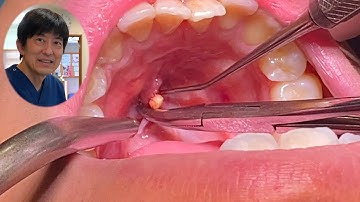

- 圧出: 医師が器具を使って扁桃を軽く圧迫し、結石を押し出します。

【唾石症/22歳社会人】顎下腺唾石の摘出手術ノーカット(口腔外科専門医 安原豊人)

安原歯科医院チャンネル